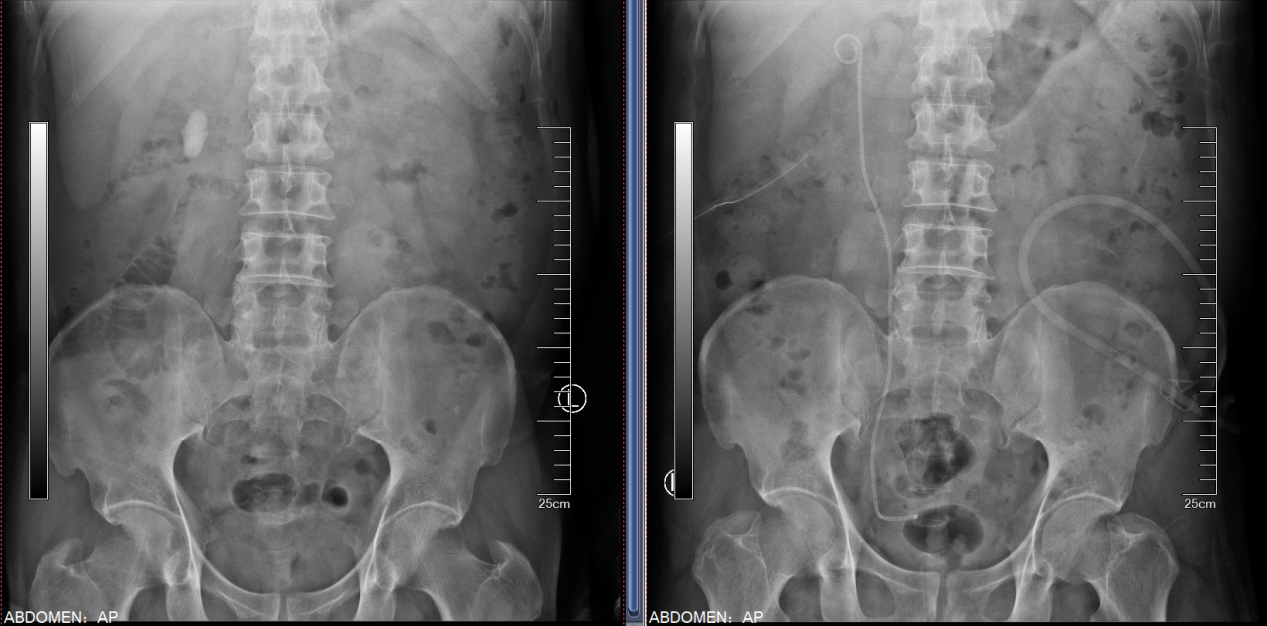

患者双肾结石多年,既往有多次结石手术病史,因为右腰部疼痛入院,检查后发现患者双肾多发结石。左侧为完全“鹿角型”结石,结石充满了整个肾脏,右侧输尿管也有多颗结石。浦金贤主任指出,患者双肾结石负荷大,左侧尤甚,且合并右侧输尿管结石,手术难度大,风险高,需优先保护肾脏功能,解除梗阻,尽可能彻底清除结石,减少术后再发概率。

经过科室讨论,周守军主任决定以分期手术的方式,借助智能控压清石系统,通过输尿管软镜处理右侧肾及输尿管结石。而对于左侧的无积水完全“鹿角型”结石,周主任在手术过程中一期采用标准通道经皮肾镜,结合第五代EMS超声弹道碎石系统清除结石主体,二期通过输尿管软镜配合末端可弯曲负压吸引鞘清除残余结石。术后患者恢复迅速,解决了困扰多年的结石问题。

患者在外院检查发现:CT提示右肾多发结石,右侧肾盂及输尿管扩张积水。患者既往曾多次行输尿管镜手术,存在右输尿管狭窄病史。患者入院后浦金贤主任组织科室讨论指出,患者右肾下盏多发结石,且部分位于下盏小盏,角度刁钻,手术难度大,单一经皮肾镜或输尿管软镜难以完全清除结石。周守军主任带领结石团队全力准备手术,采取斜仰卧位经皮肾镜-输尿管软镜(PCNL-RIRS)双镜联合的手术方式,一期手术彻底清除结石,复查结石无残留,达成理想的治疗效果。

该例患者2年来出现右腰部反复疼痛,伴尿频尿急尿痛、肉眼血尿。来我院前曾经在外院检查B超提示右肾结石,选择进行保守治疗并定期复查。近期患者再发右腰部疼痛来我院就诊,B超检查提示:右肾结石,右肾囊肿。尿常规检查提示:白细胞:1332个/ul,予以口服抗生素治疗1周后收住入院。入院后进一步完善相关检查,CT检查提示:右肾结石,大小约3.1x1.8cm,右肾囊肿大小约5.0x3.5cm,复查尿常规:白细胞:191个/ul。浦金贤主任带领科室成员仔细阅片后指出,患者结石位于肾盂输尿管连接处,负荷较大,且尿常规检查显示白细胞较高,考虑结石伴发感染可能性大,需严格控制感染,术中应注意肾盂内压力,减少术后严重感染风险。同时,患者右肾囊肿体积较大,可以考虑同次手术一并处理。根据患者病情特点,周守军主任采用腹腔镜微创手术的方式,一期手术同时行腹腔镜肾盂切开取石和腹腔镜肾囊肿去顶术,将结石完整取出、肾囊肿去顶减压,一次手术解决两个问题。患者术后迅速康复,未出现发热、尿瘘等并发症,顺利出院。